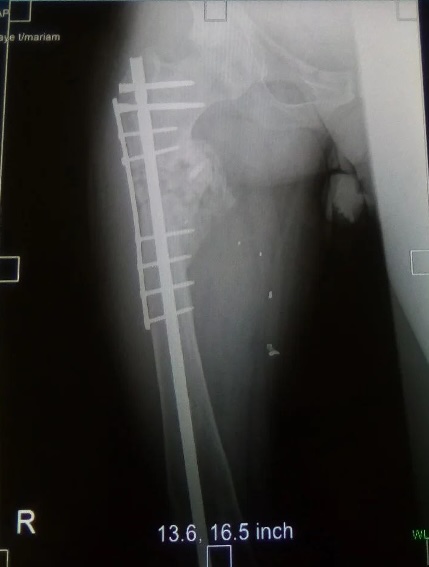

I was also able to meet the first two spine surgery fellows at AaBET. They are both neurosurgeons. The plan after next year is to alternate orthopedic with neurosurgery spine fellows. In addition to their teaching at AaBET, they are mentored by Dr Fasil Mesfin of Univeristy of Missouri, with whom they have weekly cases conferences. They were excited to show me two massive spine tumors they just operated on, one a giant, dumbbell shaped neurofibroma of the lower thoracic spine with bone involvement and preoperative paraparesis; the other a huge aneurysmal bone cyst of posterior lumbar element. Both needed pedicle screw instrumentation and big exposures. I am not a spine surgeon but the operative photos and postop xrays were very impressive.